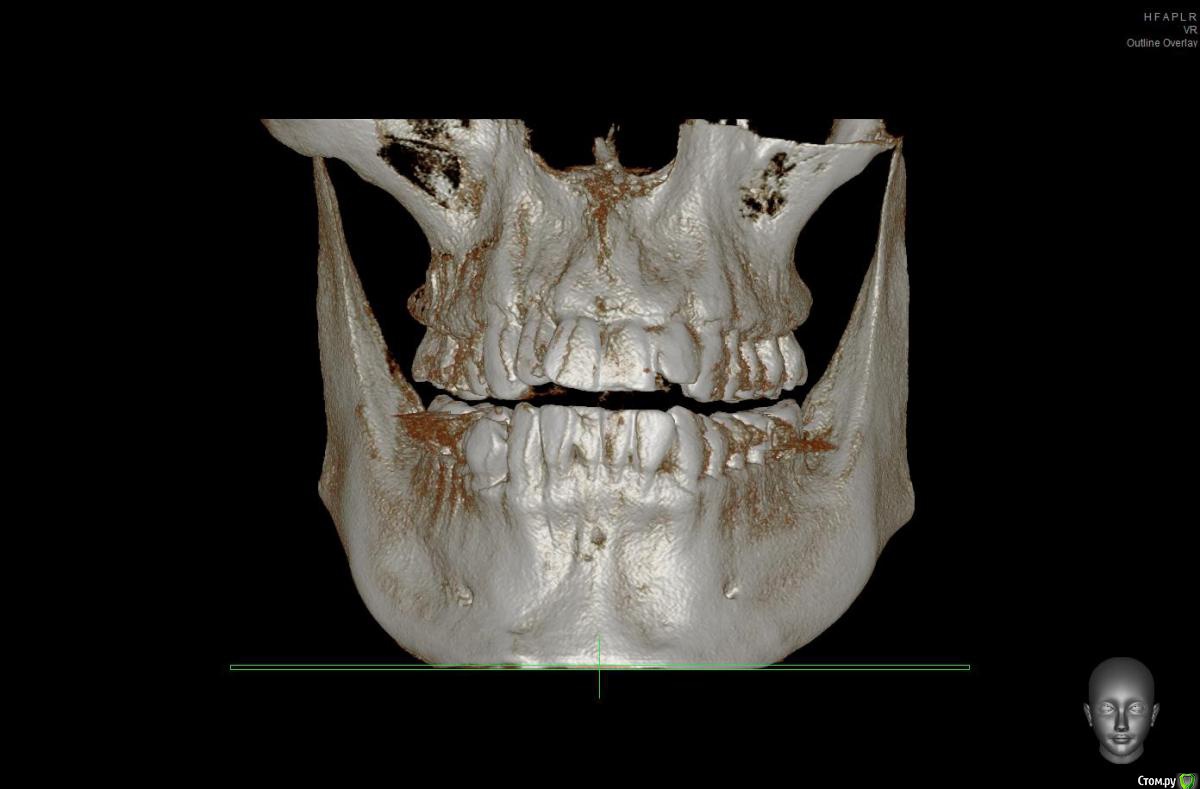

Brigita Опубликовано 1 апреля, 2017 Поделиться Опубликовано 1 апреля, 2017 Прошу уважаемых специалистов ответить на несколько моих, возможно глупых, вопросов:1) Что с моими челюстями не так (диагноз)? 2) Насколько оправдано использовать подобные аппараты в моем случае?3) Возможно ли другая тактика лечения? 1. Все так, как говорит Ваш ортодонт. Верхняя микро-ретро-гнатия, нижняя макрогнатия.2. Ну что значит - насколько? Есть такая тактика лечения, в Вашем возрасте тяги могут и не сработать, но камуфляж ( то есть видимость правильного прикуса) можно получить.3. Ортогнатическая операция - верхняя челюсть ставится вперед, нижняя назад. До и после - лечение на брекет-системе Ссылка на комментарий

Brigita Опубликовано 3 апреля, 2017 Поделиться Опубликовано 3 апреля, 2017 Смысл невелик - Небольшое расширение на зубоальвеолярном уровне. Но проверить надо, есть ли куда расширятся- это можно на кт сделать. 1 Ссылка на комментарий

solitary Опубликовано 3 апреля, 2017 Автор Поделиться Опубликовано 3 апреля, 2017 Brigita, огромное вам спасибо, что находите время отвечать на мои вопросы http://i12.pixs.ru/storage/3/3/1/1jpg_6052132_25752331.jpgКТ у меня есть, сделанная в рентгенодиагностическом центре Пикассо. Если потребуется, я могу выслать. Сделал скриншот ВЧ, но наверное неправильно выставил оси в программе. Посмотрите пожалуйста. Ссылка на комментарий